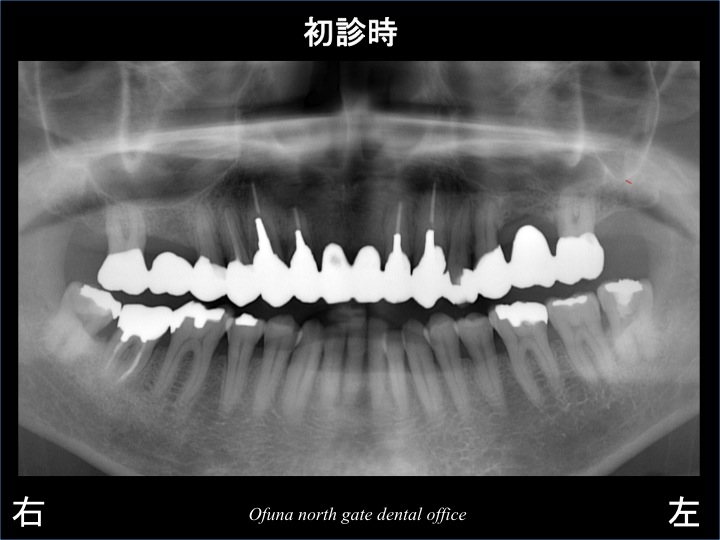

以下は初診のレントゲンです。

上顎前歯部のブリッジがグラグラするとのことで来院されました。

診査の結果、上顎前歯部ブリッジの右側の土台となっている歯が虫歯が進行しており、歯根破折 していたのです。

このレントゲンでは分かりづらいのですが、

歯の根が、まっぷたつに折れていたのです。